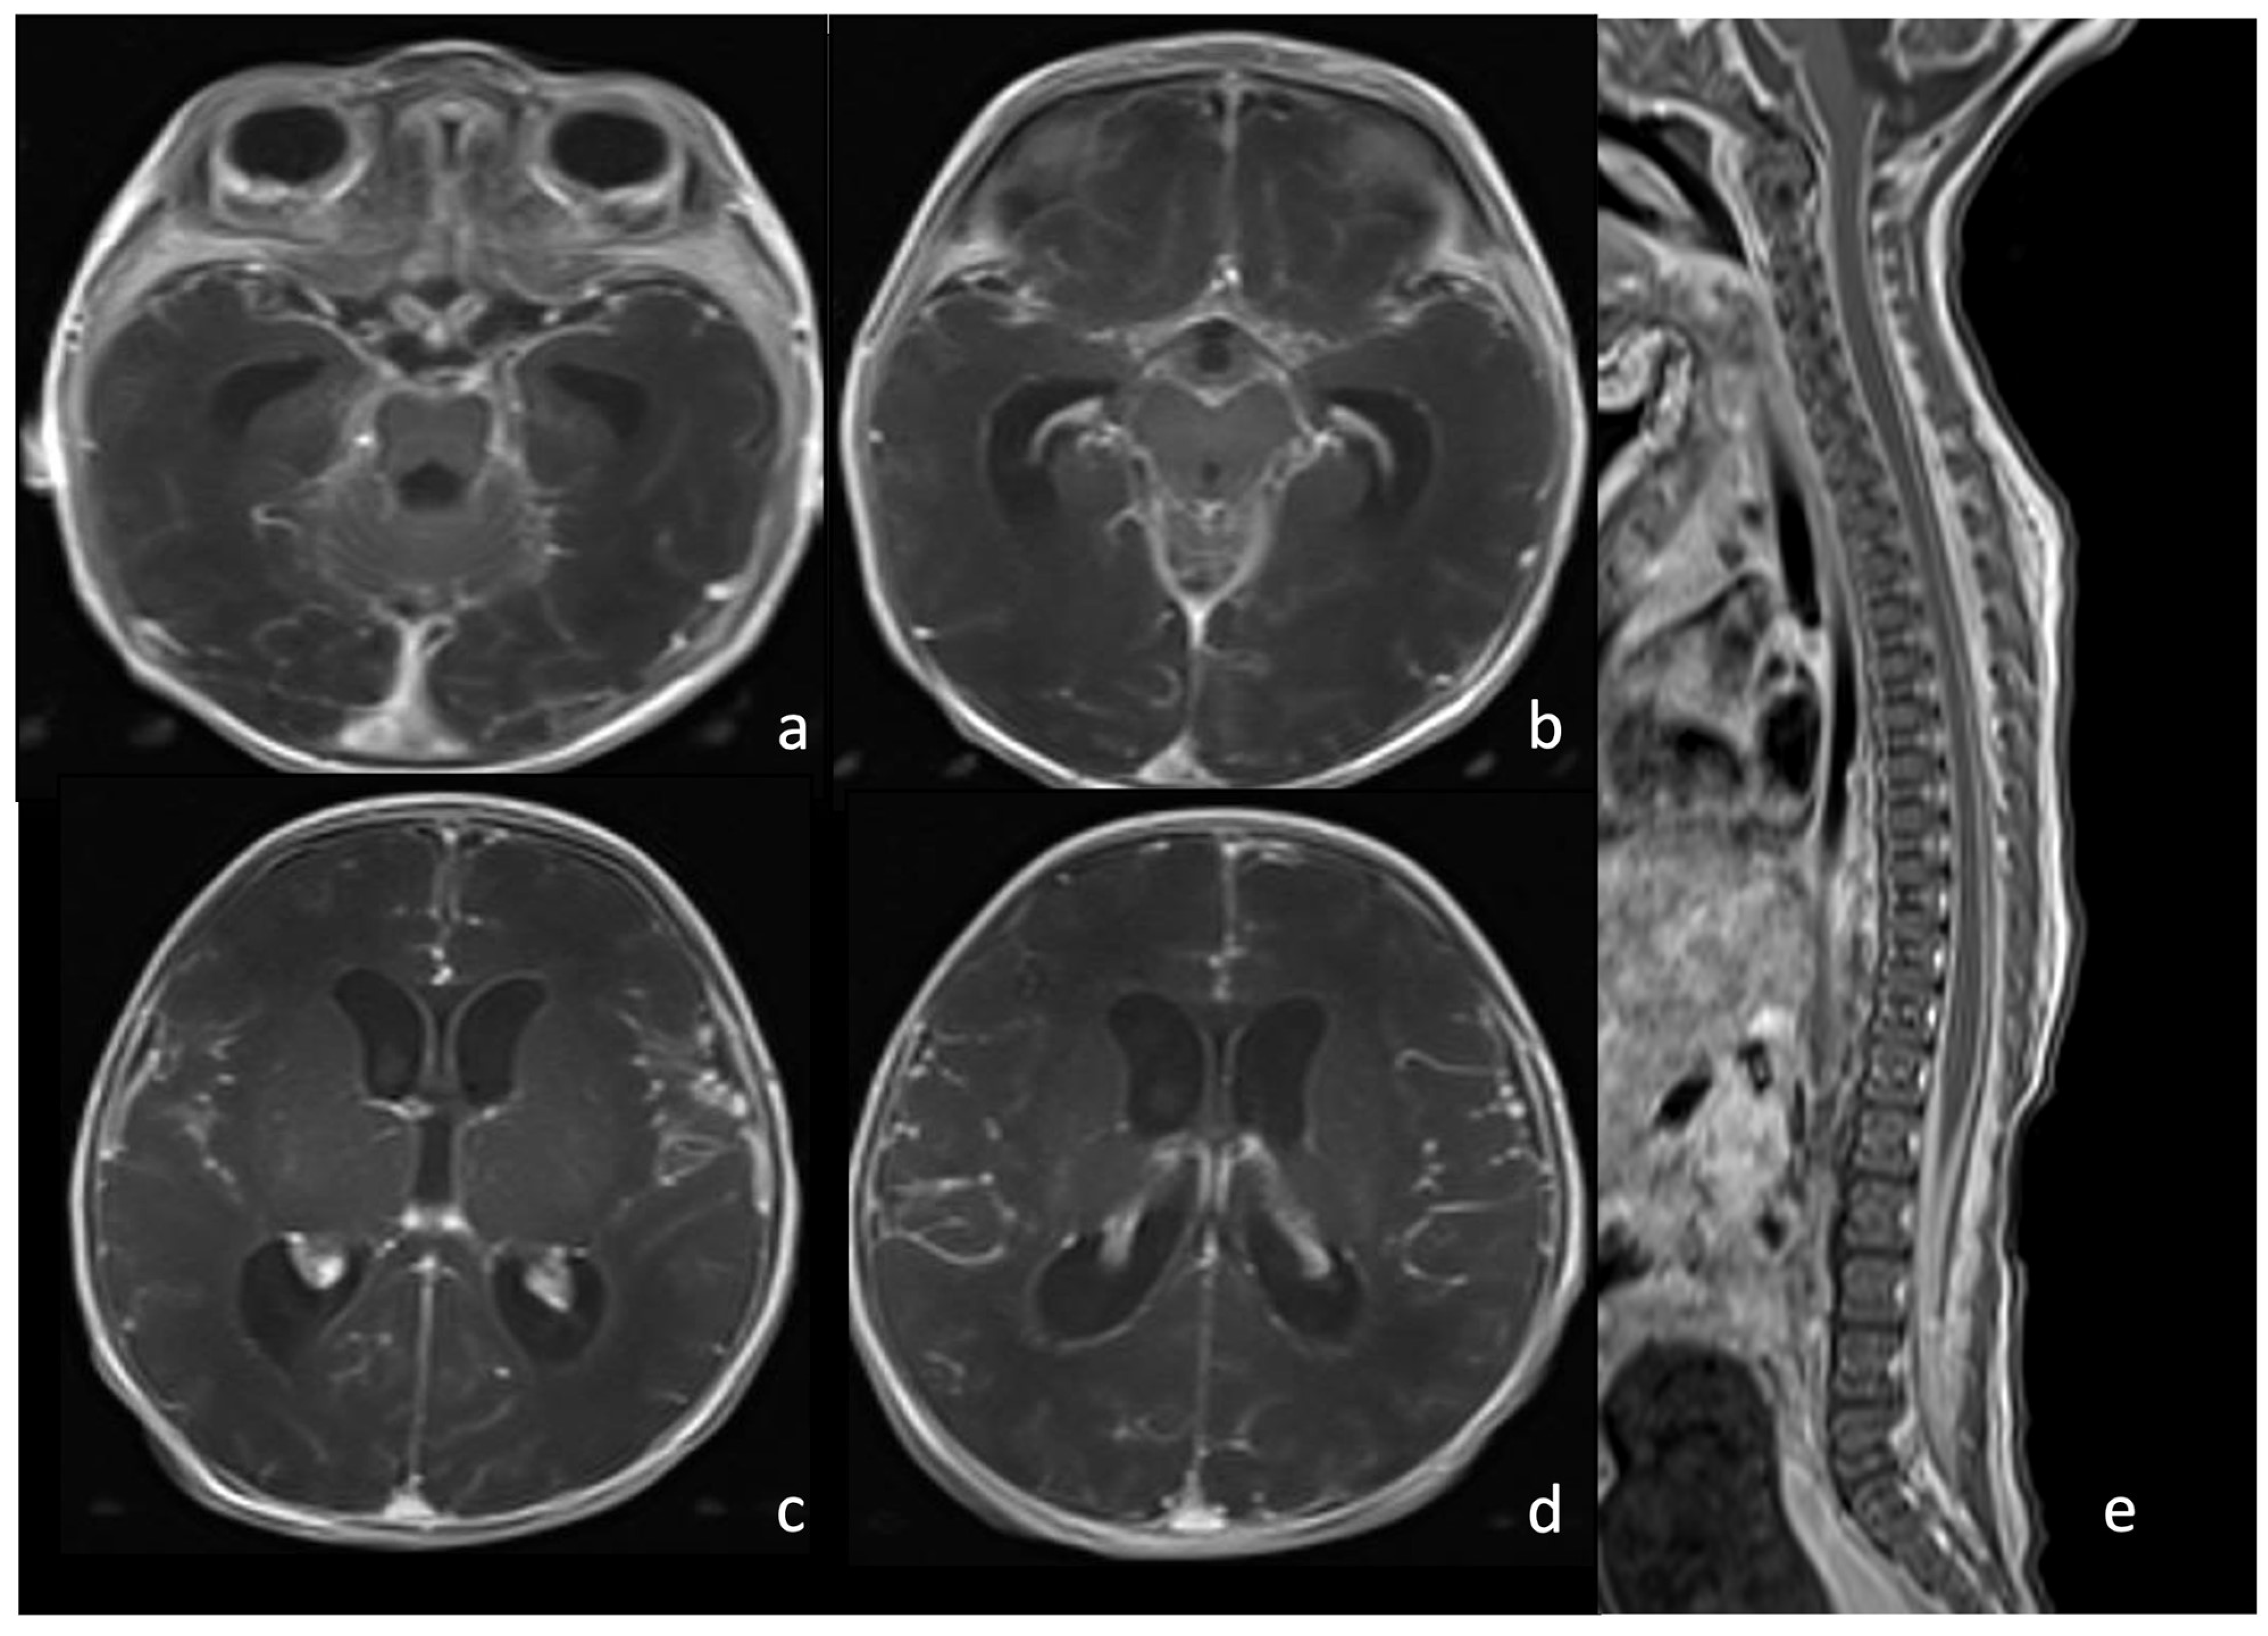

7.2. Listeria Monocytogenes

5.3. Ventriculomegaly and Hydrocephalus

5.4. Effusions and Empyema